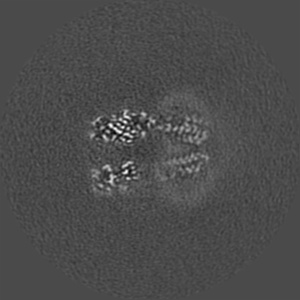

Cryo-EM structure of human full-length beta3delta GABA(A)R in complex with nanobody Nb25

Single-particle2.9 Å

Sample: Human full-length beta3delta GABA(A)R in complex with Nanobody Nb25